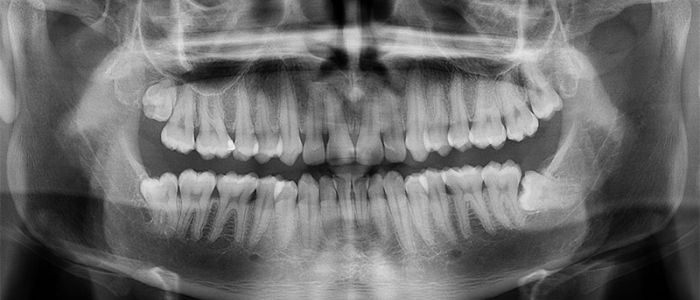

Radiografías Extraorales

Las radiografías extraorales se emplean cuando no es factible obtener información diagnóstica adecuada en las series de radiografías intraorales, es así que son utilizadas para observar un área grande de los maxilares y del cráneo en una sola radiografía. Los exámenes radiográficos extrabucales tienen el propósito de evaluar áreas grandes del cráneo, dientes impactados y patrones de erupción, crecimiento y desarrollo; examinar la extensión de lesiones grandes, traumatismos, articulación temporomandibular. Son de mucha utilidad principalmente en Ortodoncia y Cirugía Bucal.

Existen varias radiografías extraorales entre las cuales se tiene: